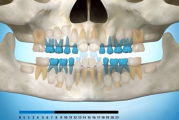

Normaalne lõikumise järjekord 7,5-aastselt:

Normaalse jäävhammaskonna pilt küljelt ja eest vaadatuna.